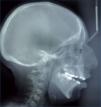

Tanto las malformaciones y deformidades faciales requieren una cefalometría en telerradiografía de cráneo y cara. Esta permite el diagnóstico esqueletal del paciente, a través de la morfología de la calota craneal, base de cráneo y la relación del complejo maxilomandibular con respecto a ella. A su vez permite observar la posición del hueso hioides y las características de la vía aérea.

En este mismo estudio se analiza el perfil blando de los pacientes y su relación con el esqueleto facial (18,19) (Figuras 8 y 9).

Análisis estructura y arquitectural del esqueleto cráneo facial de Jean Delaire (18).

Posterior a este tratamiento uno planifica la cirugía. Esto se realiza mediante una cefalometría de perfil en una telerradiografía de cráneo y cara, de manera de objetivar la posición del maxilar y la mandíbula con respecto a la base del cráneo, la relación entre ellas mismas y las características del tejido blando relacionado.

En este estudio también se planifica la modificación de posición del maxilar y la mandíbula necesaria para el paciente y sus implicancias en los tejidos blandos asociados.